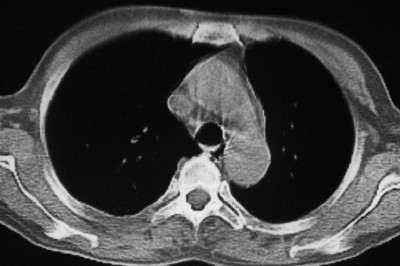

以下是引用天南地北在2007-4-10 1:49:00的发言:[br]考虑右下叶周围型肺癌伴肋骨转移。

以下是引用林建春在2007-4-10 7:35:00的发言:[br]周围型肺癌侵犯肋骨

以下是引用liuyue在2007-4-10 7:56:00的发言:[br]周围型肺癌侵犯肋骨,左肺转移。

以下是引用zhangzhongshou在2007-4-10 10:24:00的发言:[br]右肺下叶背段厚壁空洞,伴胸膜改变、肋骨破坏,其内可见死骨、周围骨质硬化,左肺可见小结节影,[br]单纯影像学更支持结核。建议进一步检查。